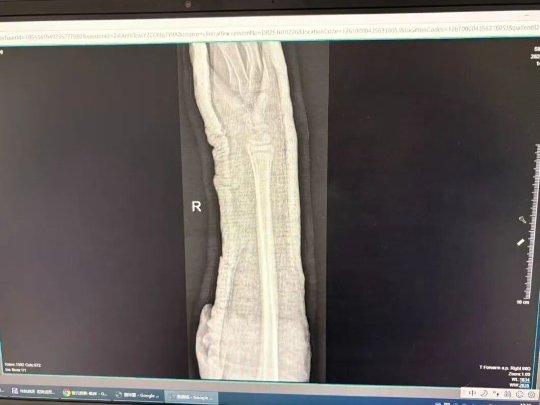

(石膏X光图示)

(夹板X光图示)